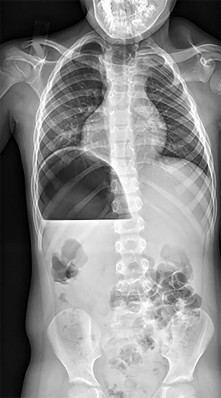

A 12-year-old obese male presents with left groin pain and an altered gait. Based on the presumed diagnosis of slipped capital femoral epiphysis (SCFE) shown in the representative radiograph, which of the following is the primary blood supply to the femoral head that is at highest risk for iatrogenic injury during percutaneous in situ pinning if the pin is placed in the posterosuperior quadrant?